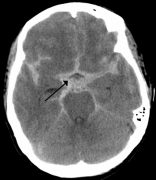

动脉瘤 是血管中有破裂危险的脆弱区域。当动脉瘤位于大脑时,我们称之为脑动脉瘤,脑内动脉瘤,或颅内动脉瘤。脑动脉瘤的形成往往需要很长一段时间,在破裂或破裂之前可能不会...

脑动脉瘤 破裂属于疾病吗?中国大约有4000万脑动脉瘤患者,每年大约1%有破裂风险,也就是说每年大概会新增40万脑动脉瘤破裂患者,而破裂出血可能导致脑损伤,甚至有40%的死亡风...

问: 脑动脉瘤破裂 后会发生什么? 答:脑动脉瘤表明血管中的薄弱区域,经常变大并暗示相应血管的膨胀。相关阅读: 脑动脉瘤破裂出血怎么办? saccular aneurysm 囊状动脉瘤 fusiform an...

颅内动脉瘤,又称脑动脉瘤,是一种脑血管疾病,由于大脑动脉或静脉管壁薄弱,导致血管局部扩张或膨胀。后循环(基底动脉、椎动脉和后交通动脉)的动脉瘤有较高的破裂风险。基底...